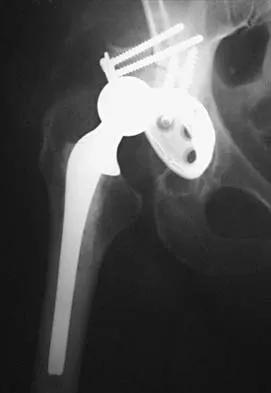

Question 51High Yield

A 38-year-old woman with metastatic thyroid carcinoma has had increasing pain in the left hip for the past 3 months. An AP radiograph and coronal T1-weighted MRI scan are shown in Figures 28a and 28b. Management should consist of

Explanation

The radiograph and MRI scan reveal a lytic lesion in the left femoral neck region that extends to the lesser trochanter. Although external beam radiation and radioactive iodine infusion may be helpful in controlling the local disease, the patient is at high risk for femoral neck fracture given the location of the lesion. Prophylactic surgery is indicated; therefore, the treatment of choice is a cemented bipolar hemiarthroplasty. The use of a compression hip screw and side plate or an intramedullary nail has a high likelihood of failure with disease progression. Postoperative treatment with radiation therapy and bisphosphonates is also indicated. Mirels H: Metastatic disease in long bones: A proposed scoring system for diagnosing impending pathologic fractures. Clin Orthop 1989;249:256-264. Swanson KC, Pritchard DJ, Sim FH: Surgical treatment of metastatic disease of the femur. J Am Acad Orthop Surg 2000;8:56-65.